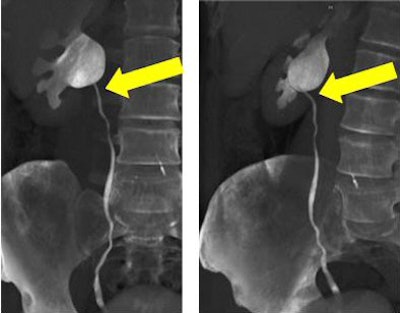

![]() |

| Volume-rendered CT images obtained during 64-channel CTU with interactive display of the collecting system and the relation of the right renal pelvis to the proximal ureter with interactive manipulation of the isotropic dataset. Images courtesy of Dr. Terri Vrtiska, Mayo Clinic, Rochester, MN. |

The left and right ureters were divided into four segments each for evaluation -- a total of 96 segments in 12 patients. In all, 90% of the segments were opacified, including all the kidneys and pelvi, she stated. One proximal ureter was not opacified in a patient with a left ureteropelvic junction (UPJ) obstruction. Three large ureters remained unopacified, but two of the three could be seen on either the prone or decompression scout view, she said. And while 10 distal ureter segments were not opacified, eight of the 10 were opacified on either the prone or decompression scout views.

"A total of 92 of the 96 segments were opacified, and if the patient with the left UPJ obstruction had been excluded, since it wasn't possible to opacify that, it would have been 92 of the 93 segments," Vrtiska said.